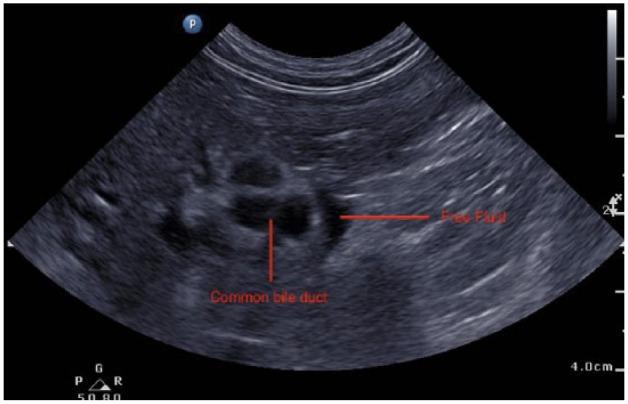

A 4-year-old male neutered domestic shorthair cat was referred for investigation of jaundice. The cat had a recent history of a skin laceration repair following trauma. Sequential serum biochemistry demonstrated increasing plasma bilirubin concentrations; abdominal ultrasonography revealed ongoing pancreatitis and apparent extrahepatic obstruction of the common bile duct. Exploratory laparotomy identified constriction of the common bile duct with foreign material (cat hair). The constricting band of hair was removed surgically; cholecystoduodenostomy was performed. Postsurgical quality of life is excellent with chronic treatment of tylosin, omeprazole and ursodeoxycholic acid.

一只4岁已绝育的雄性家养短毛猫因黄疸问题被转诊进行检查。这只猫近期有过外伤后皮肤撕裂伤修复的病史。连续的血清生化检查显示血浆胆红素浓度不断升高;腹部超声检查发现存在持续性胰腺炎以及胆总管明显的肝外梗阻。剖腹探查发现胆总管被异物(猫毛) constricted。手术切除了束发带;进行了胆囊十二指肠吻合术。术后通过长期使用泰乐菌素、奥美拉唑和熊去氧胆酸治疗,生活质量良好。